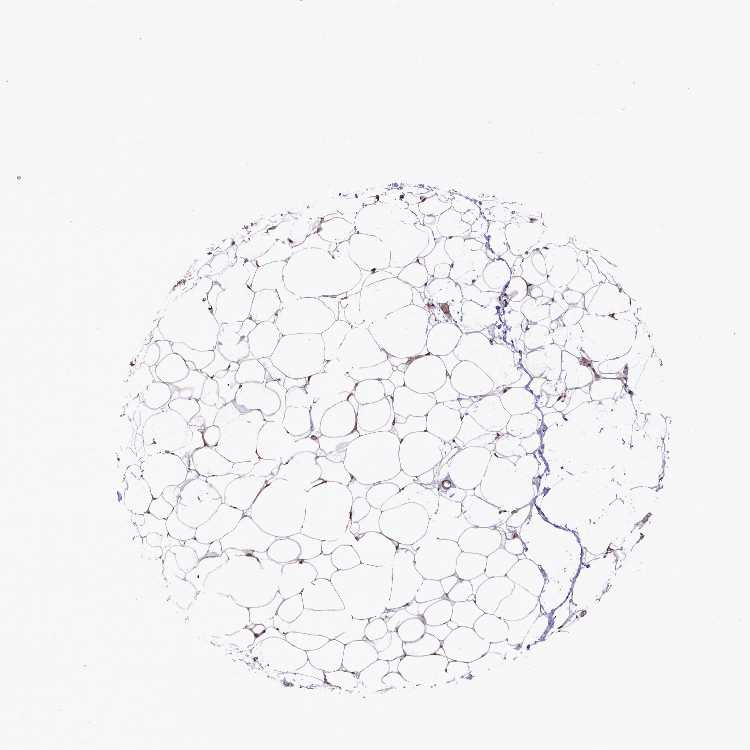

TISSUE PRIMARY DATA SOFT TISSUE Show tissue menu

SOFT TISSUE - Expression summary

SOFT TISSUE 1 - Antibody stainingi

Antibody staining in the annotated cell types in the current human tissue is reported as not detected, low, medium, or high, based on conventional immunohistochemistry profiling in selected tissues. This score is based on the combination of the staining intensity and fraction of stained cells.

Each image is clickable and will lead to virtual microscopy that enables deeper exploration of all samples and also displays staining intensity scores, fraction scores and subcellular localization as well as patient and tissue information for each sample.

Antibody HPA037646Antibody HPA043891Antibody CAB033765Antibody CAB079995

Chondrocytes MediumMediumHigh-

Fibroblasts MediumNot detectedNot detectedNot detected

Peripheral nerve -Not detectedMediumNot detected